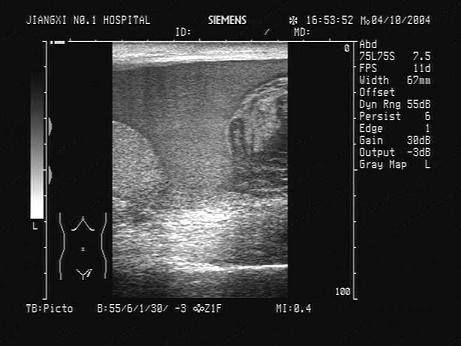

问题 某患者,左阴囊肿大,疼痛,数小时前曾与人殴斗。根据超声声像图,最可能的诊断为?(?)

选项 A.睾丸鞘膜积液 B.阴囊内血肿及血块 C.睾丸破裂 D.睾丸扭转 E.睾丸肿瘤

答案 B